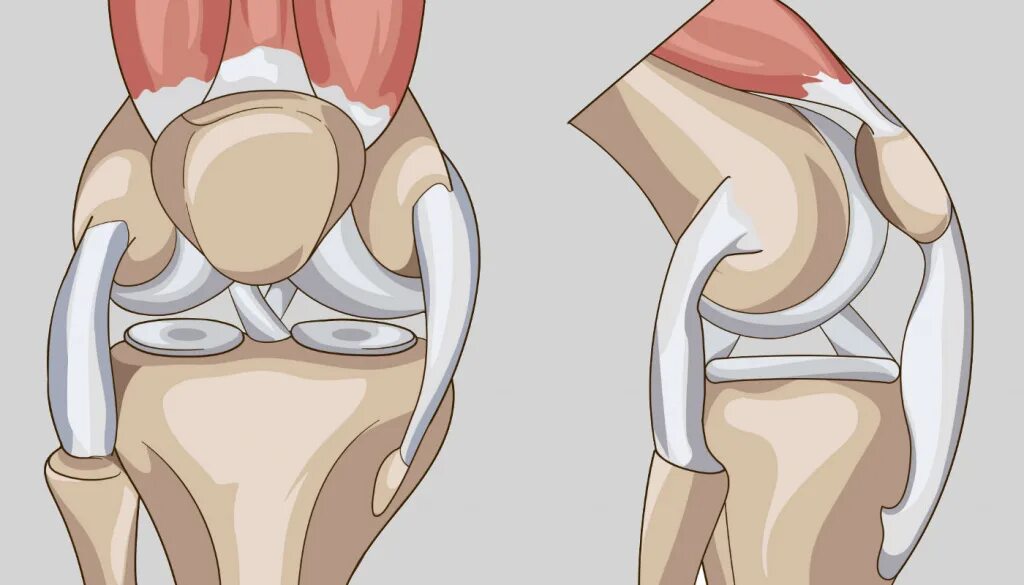

Разрыв коленного сустава 3 степени